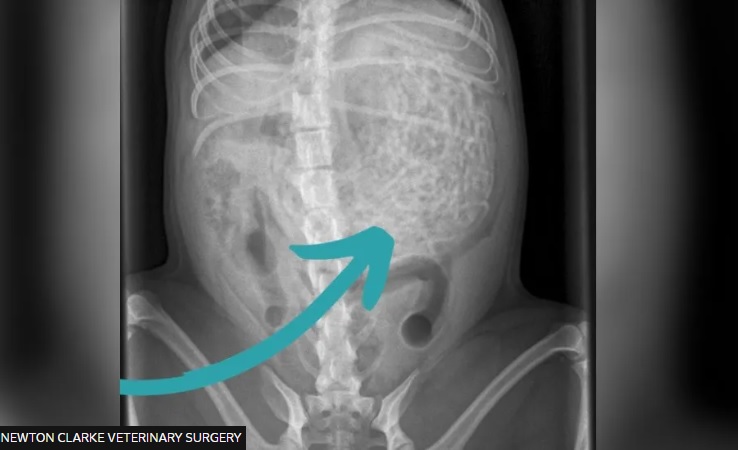

Dopo 33 anni di coma, a 60 anni, è morta Luigina Brustolin. Il 23 maggio 1992 la...